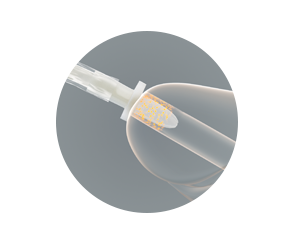

Beschermende inbrengtip

- helpt tijdens het inbrengen de steriele katheter te beschermen tegen bacteriën die zich in de eerste 15 mm van de plasbuis bevinden

- helpt het risico te verminderen dat bacteriën in de urinewegen terechtkomen

Bewezen bescherming tegen pathogenen – beschermende tip

De beschermende tip helpt het risico sterk te verminderen dat bacteriën tijdens het inbrengen in de urinewegen worden gebracht. Onderstaande illustraties tonen de effectiviteit aan bij gebruik bij mannen.

De katheter wordt tot in de tip geschoven, waarna de tip in de urethra wordt ingebracht.

De beschermende tip helpt voorkomen dat de katheter in contact komt met bacteriën die zich voornamelijk in de eerste 15 mm van de urethra bevinden.

De beschermende tip helpt voorkomen dat de katheter besmet raakt.

Klik hier voor een samenvatting van het klinisch en laboratoriumbewijsmateriaal dat aantoont dat de beschermende tip de kans op het inbrengen van bacteriën in de urinewegen vermindert. Het verminderen van het inbrengen van bacteriën zou het risico op urineweginfecties die zijn gerelateerd aan het gebruik van een katheter, kunnen verminderen.